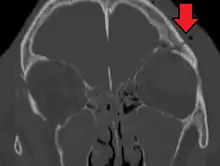

A basilar skull fracture is a break of a bone in the base of the skull.[1] Symptoms may include bruising behind the ears, bruising around the eyes, or blood behind the ear drum.[1] A cerebrospinal fluid (CSF) leak occurs in about 20% of cases and may result in fluid leaking from the nose or ear.[1] Meningitis occurs in about 14% of cases.[2] Other complications include injuries to the cranial nerves or blood vessels.[1]

A basilar skull fracture typically requires a significant degree of trauma to occur.[1] It is defined as a fracture of one or more of the temporal, occipital, sphenoid, frontal or ethmoid bone.[1] Basilar skull fractures are divided into anterior fossa, middle fossa and posterior fossa fractures.[1] Facial fractures often also occur.[1] Diagnosis is typically by CT scan.[1]

- Cerebrospinal fluid rhinorrhea

- Bleeding (sometimes profuse) from the nose and ears

- Hemotympanum